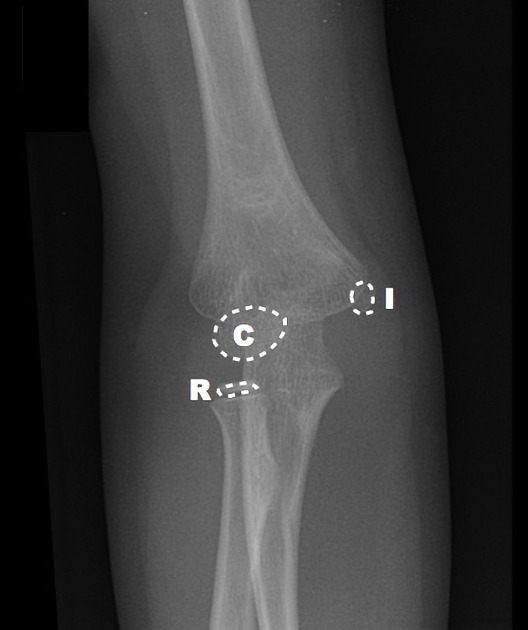

Elbow Interpretation Roadmap: CRITOE

More pragmatic and utilitarian than a prosaic mnemonic, CRITOE helps us to remember the order of ossification of the pediatric elbow.

Although children develop at different rates, the order of ossification is programmed into us.  Images courtesy of Radiopaedia.

Internal Epicondyle

By the age of five, the capitellum and radial head are no longer little floating balloons, but now taking on shapes that resemble what they will look like as an adult. By age five, you’ve grown out of balloons, and have moved on to Frisbees.  The internal epicondyle (meaning the medial epicondyle) starts to ossify by age five – a little bony Frisbee.

External Epidondyle

By age 11, you start to ossify your external epicondyle (lateral epicondyle).

CRITOE gives us the order of ossification for the pediatric elbow – capitellum, radial head, internal epicondyle, trochlea, external epicondyle, and olecranon — typically occurring at year 1, 3, 5, 7, 9, and 11 – remember the order is the most important thing – all ossification centers should be accounted for.  Make sure one is not missing – or where one has been “created” traumatically.